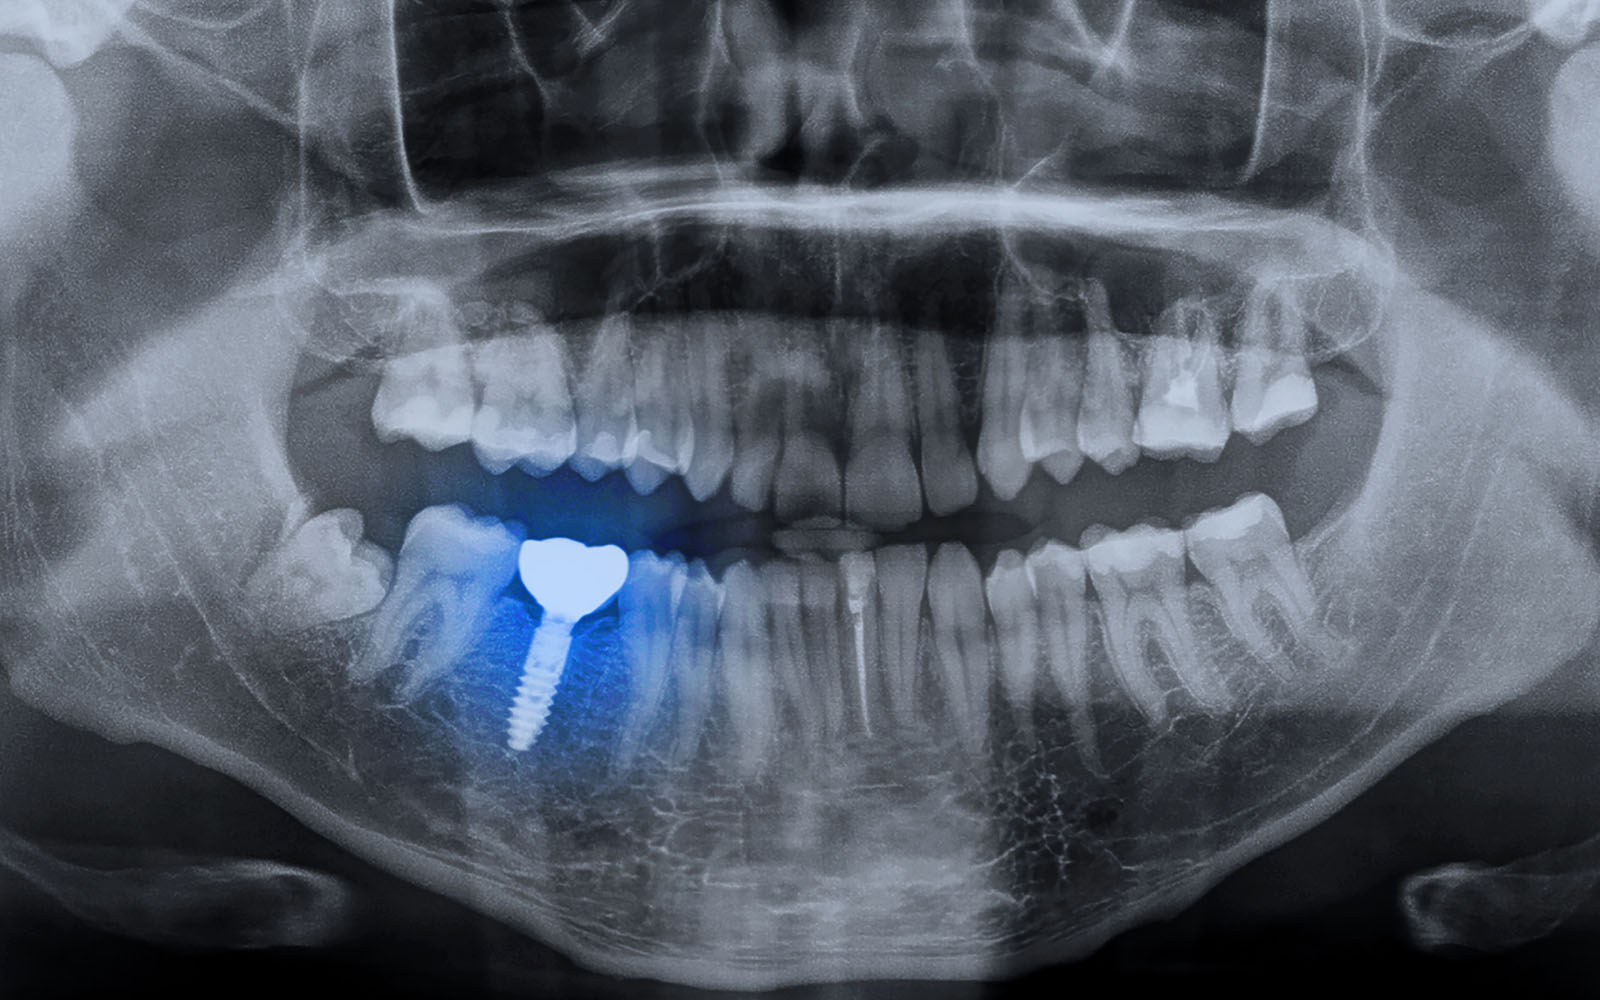

The treatment itself involves placing a small titanium screw (dental implant) into the jawbone. These remain out of sight and provide an artificial root, to which prosthetic teeth can be attached.

Dental implant surgery does not take long and thanks to the use of anaesthetic, it is in most cases, a pain-free experience. Once the procedure is complete, it is normal to wait for the implant to intgerate with the jawbone and during this time you will be fitted with a temporary restoration. After approximatley 6 weeks the final crown, bridge or denture can be fitted and provided you maintain good oral hygiene, your dental implants will be a seamless replacement for missing teeth and potentially last a lifetime.